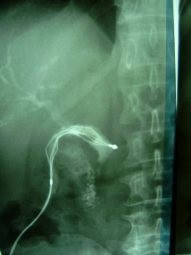

Litotripsia y extracción de cálculo de coledoco residual

Envíado por Dr. Carlos Miguel Zavaleta Consuegra